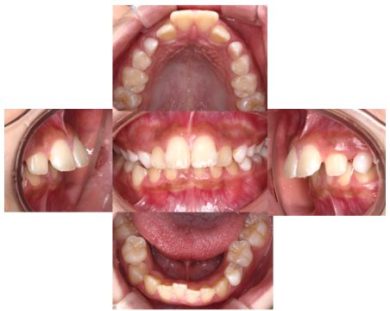

治療開始から10か月→

この男の子は10か月間でここまで改善しました。まだまだ、改善途中ですがお子さんの成長を利用すると短期間で改善が期待できます。この子が10か月間やってきたことは?

- 起きているときに1時間マイオブレイスをお口にいれる(テレビを見ながら)、寝るとき入れる。

- 1日5分間動画を見ながら口周りの悪い癖を取るトレーニングをすることだけです。

それによって顎の骨の成長方向と成長量を改善できた結果、歯並びもここまで改善しました。